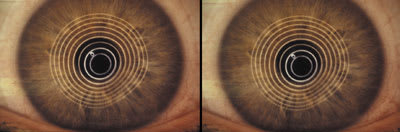

| Figure 1. Patient VB OD (left) OS (right). | Figure 2. Videokeratography OU. |

| Figure 3. New reverse geometry SCLs OU. | Figure 4. Photokeratoscopy OD: without SCL (left) with SCL (right). |

Figure 5. Photokeratoscopy OS: without SCL (left) with SCL (right).  |